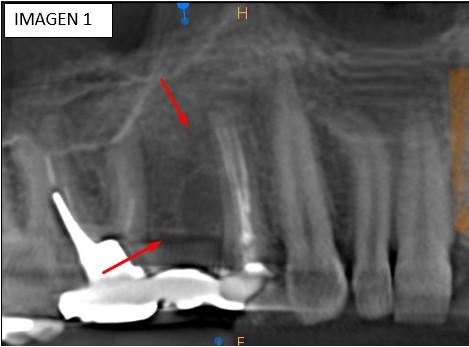

En una vista panorámica (imagen 1) se observa en zona desdentada y marcada por la flecha una imagen hipodensa de bordes corticalizados y bien definidos, redondeados, bien circunscriptis, ubicado lateralmente en reborde alveolar de pieza dentaria 15. Esta lesión también lo podemos valorar en una vista transaxial (imagen 2).

En la vista axial (imagen 3) observamos como la lesión adelgaza la tabla ósea vestibular, comportamiento de un Quiste, en este caso Residual. Además, se observa una lesión de furca en pieza dentaria 14 (ver imagen 4).